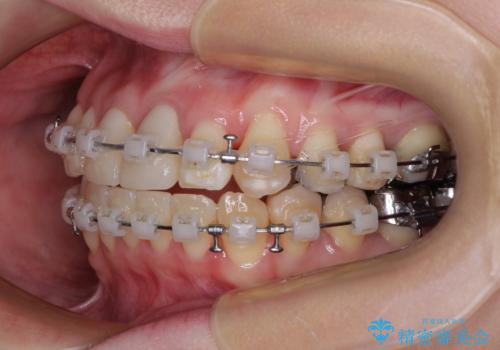

- 矯正装置

- クリアブラケット

- 2年2ヶ月

- 10-30回

前歯を早々に仮歯に置き換えたことで、矯正治療に意欲的に臨んでくださいました。

口元が前方に突出することもなく、綺麗に仕上げることができました。